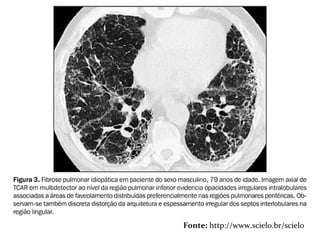

 TCAR  Extensãodo acometimento pulmonar e fase da dça. ▪ Precoce: áreas em vidro fosco ▪ Avançada: faveolamento FIBROSE PULMONAR IDIOPÁTICAFIBROSE PULMONAR IDIOPÁTICA

 Padrão definitivo– Todos os 4 critérios são necessários:  Predominância nas bases e regiões subpleurais;  Anormalidades reticulares;  Faveolamento com ou sem bronquiectasias de tração;  Ausência de todos os 7 critérios inconsistentes com o padrão de UIP FIBROSE PULMONAR IDIOPÁTICAFIBROSE PULMONAR IDIOPÁTICA

FIBROSE PULMONAR IDIOPÁTICAFIBROSEPULMONAR IDIOPÁTICA Fonte: http://www.scielo.br/scielo